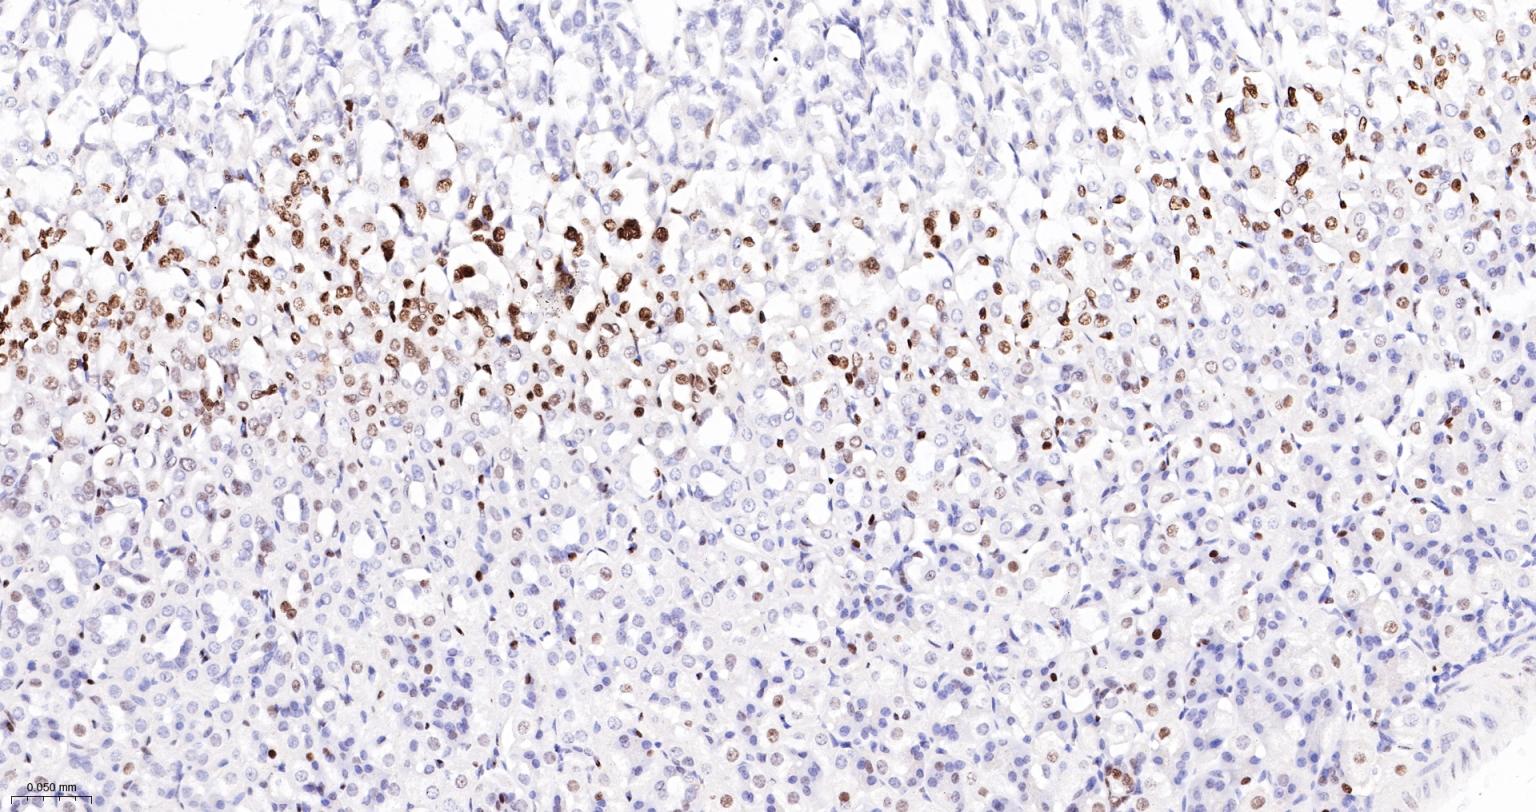

Paraformaldehyde-fixed, paraffin embedded Human Spleen; Antigen retrieval by boiling in sodium citrate buffer (pH6.0) for 15 min; The section was incubated with FUBP1 Monoclonal Antibody, Unconjugated (bsm-60625R) at 1:200 overnight at 4°C, followed by conjugation to the bs-0295G-HRP and DAB (C-0010) staining.

Paraformaldehyde-fixed, paraffin embedded Rat Spleen; Antigen retrieval by boiling in sodium citrate buffer (pH6.0) for 15 min; The section was incubated with FUBP1 Monoclonal Antibody, Unconjugated (bsm-60625R) at 1:200 overnight at 4°C, followed by conjugation to the bs-0295G-HRP and DAB (C-0010) staining.

Paraformaldehyde-fixed, paraffin embedded Mouse Spleen; Antigen retrieval by boiling in sodium citrate buffer (pH6.0) for 15 min; The section was incubated with FUBP1 Monoclonal Antibody, Unconjugated (bsm-60625R) at 1:200 overnight at 4°C, followed by conjugation to the bs-0295G-HRP and DAB (C-0010) staining.